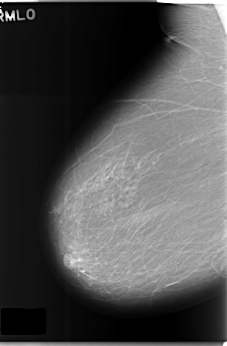

C_0176_1.RIGHT_MLO

RIGHT_MLO LINES 5880 PIXELS_PER_LINE 3848 BITS_PER_PIXEL 12 RESOLUTION 50 NON_OVERLAY